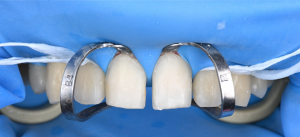

※ラミネートベニアを装着する際の様子

ラミネートベニアなどのセラミック治療を長く安定して使っていただくためには、接着する際の環境がとても重要です。

当院では、上記の写真のように、ラバーダムと呼ばれるゴムのシートを使用し、歯を唾液や湿気からしっかり隔離した状態で接着処理を行っています。

この方法により、接着の精度を高め、治療後の安定性に配慮しています。

※隣在歯の保護

接着の処置中にとなりの歯を傷つけないようにするため、歯の周囲をテフロンテープで保護しています。